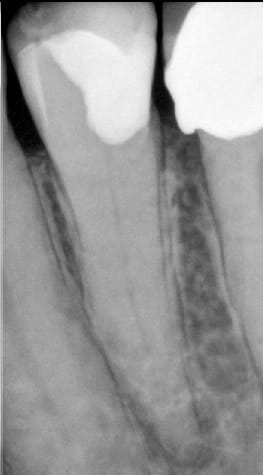

Ci-dessous, retraitement des canaux mésiaux de la 46 au mono-cone + MTA en février 2014. Patient revu aujourd'hui pour le retraitment de la 47.

46 47 avant eiobhz - Eugenol

46 47 08022014 wtbemp - Eugenol

46 47 15022014 p86o9h - Eugenol

46 47 26012015 aoqw5g - Eugenol